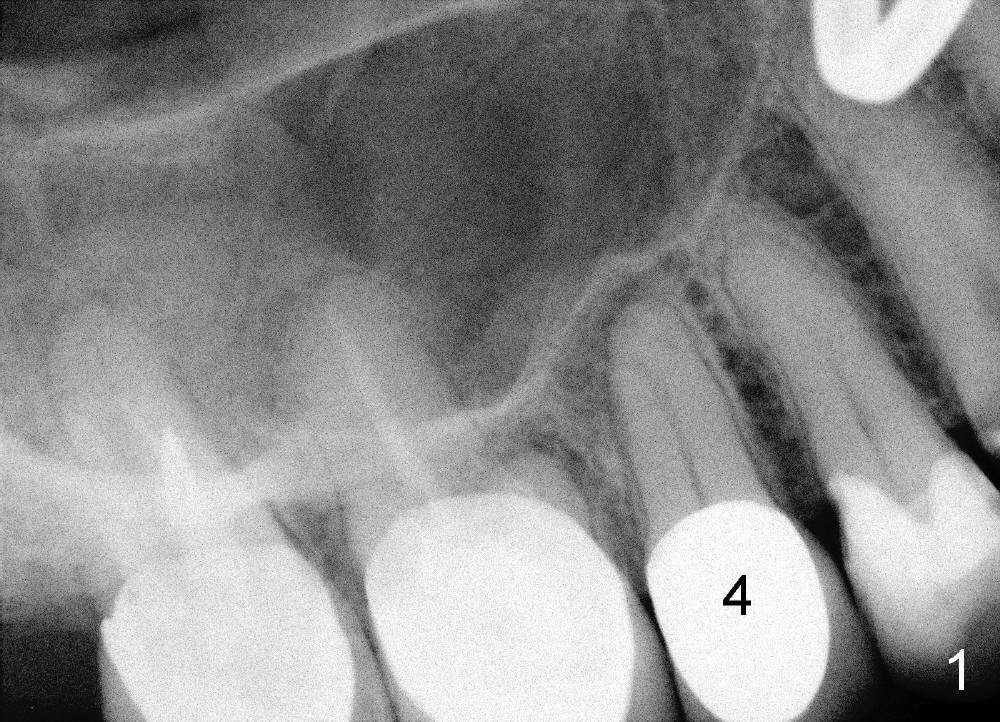

四十八岁俄国女人去年因右上牙痛就诊,右上五(图一:美国称为四号牙)有牙冠修复,叩诊疼痛,牙髓测定死髓牙,术前很难理解为什么根管末端弯曲(图一':红箭头;白箭头代表根尖阴影范围),根管扩大至40/.06(rotary file),插入同一号牙胶尖(图二箭头),好像挺接近弯曲根管顶端,但是离根尖还有一些距离,从牙冠打洞,里面一片漆黑,使用两倍半放大镜(loops),也无能为力,最后完成根管充填(图三),看上去挺不错,顺着弯曲根管走(箭头),有些得意洋洋,最末端部分(上下箭头之间)可能被糊剂充填。欣慰的是术后疼痛消失,一年后病人因右下桥松动而再次就诊,检查表明七断裂需要拔牙,植牙,由于下牙槽神经在根尖片中看得不清楚,她牙齿问题很多,便拍摄全口CT。右上五CT显示根尖阴影好像没有减少多少(图四箭头,与图一',图二,图三对比),所以根管末端弯曲有一定特殊意义,那是什么呢?